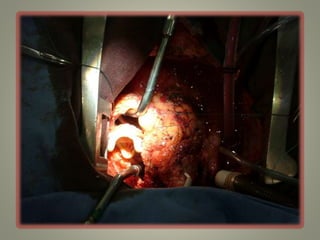

Técnica Cirúrgica